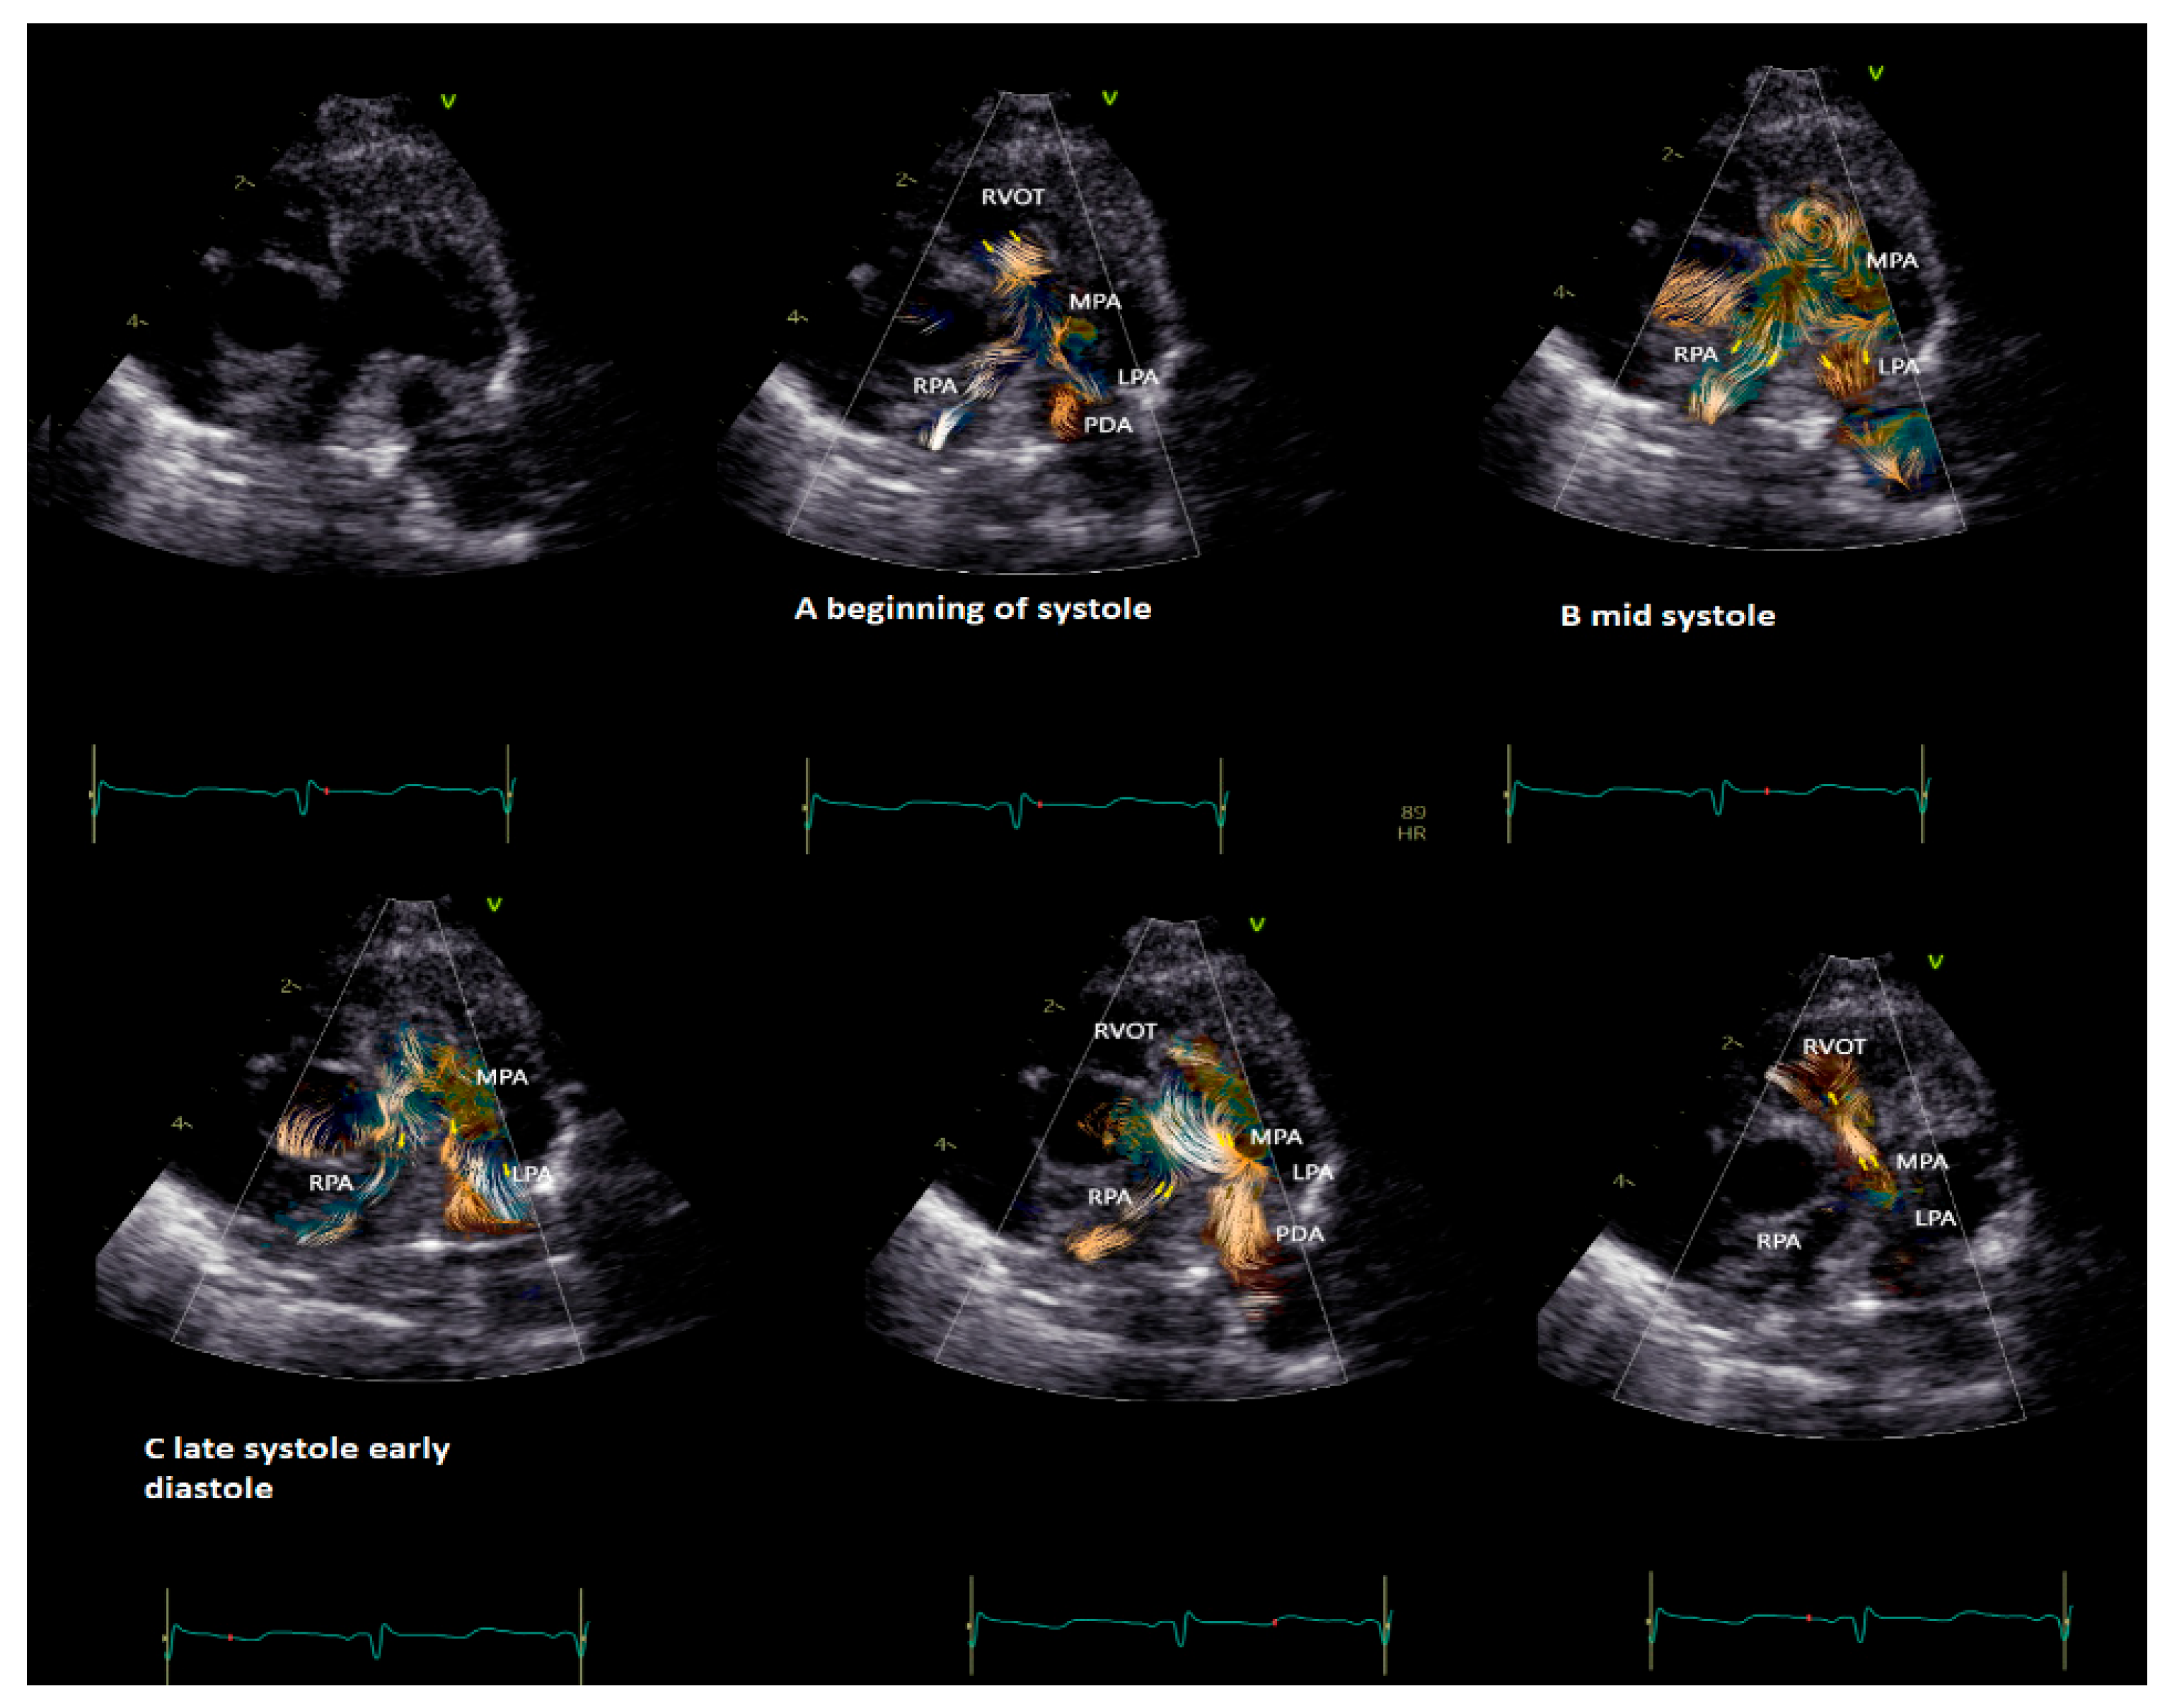

BST may be employed as a complementary tool to color Doppler for a better and more intuitive understanding of flow dynamics across the cardiac chamber and main vessels [11,13]. BST may be helpful to understand the turbulence occurring at the level of the main vessel’s due stenosis, the formation of vortex after the stenosis, and their contribution to the post-stenotic dilatation [5,11,13,16,17]. Similarly, BST may be helpful for a deeper understanding of vortex formation and energy loss in heart chambers due to regurgitant flow [16]. Vortices in the stenotic vessels by vector flow imaging were first described by Honda and colleagues in 2014 in a 15-month-old baby with pulmonary stenosis and post-stenotic dilatation [5]. The authors demonstrated that after percutaneous valvuloplasty, the main pulmonary artery diameter, the vortex dimension, and the energy loss all diminish [5]. More recently, BST has been applied for the evaluation of stenotic and regurgitant semilunar valve disease, with a special focus on aortic disease [8,19]. In Figure 3, we provide an example of vortex propagation in a child with pulmonary stenosis after pulmonary valvuloplasty. BST echocardiography has been also applied to study the characteristic of pulmonary artery blood flow in children with pulmonary hypertension [21]. In 18 children < 10 years with pulmonary hypertension [21], the energy loss vector complexity and diastolic vorticity in the main pulmonary artery were significantly higher in both systole and diastole compared to age-matched controls (e.g., systolic energy loss 4.84 vs. 2.42 mW/m; p = 0.01, systolic vorticity 0.21 vs. 0.04, p = 0.003; diastolic energy loss 0.69 vs. 0.14 mW/m; p = 0.01, diastolic vorticity 0.13 vs. 0.05, p = 0.04). Vorticity in the main pulmonary artery (15.2 vs. 4.4 Hz; p = 0.001) was also higher in children with pulmonary hypertension compared with controls [21].

Figure 3. Vortex in the pulmonary valve in a neonate (4.5 kg weight) with pulmonary stenosis after valvuloplasty. The short-axis view shows vortex propagation into the pulmonary arteries during the cardiac cycle. (A) The vortex at the level of the pulmonary valve (beginning of the systole), (B) propagating into the main pulmonary artery (mid-systole) and into (C) pulmonary artery branches (late systole and early diastole). In the last two images, it is possible to observe the flow coming from the patent ductus arteriosus (PDA) that impacts the antegrade pulmonary flow and subsequently the flow coming from the PDA only that directly reaches the RVOT through the insufficiency of the pulmonary valve. The BST movies were acquired at frame rates ranging from 400 to 500 fps in non-sedated infants. Clips of 2 cardiac cycles were stored using medium (66 cm/s), to low (53 cm/s) Nyquist limits.